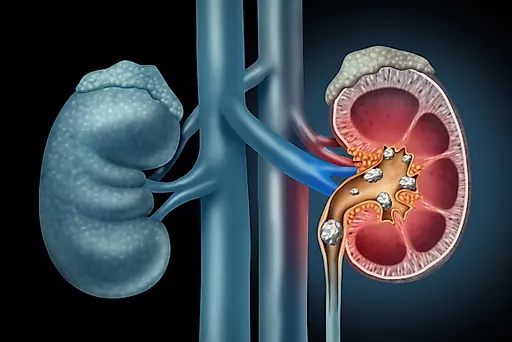

Мочекаменной болезнью называют патологию, характеризующуюся формированием конкрементов в органах мочевыделительной системы. Чаще всего камни образуются в почках, мочеточниках и мочевом пузыре. Клинические проявления недуга зависят от размера конкрементов, наличия воспалительного процесса и других факторов, однако к наиболее распространенным осложнениям болезни врачи относят закупорку мочеточника, невыносимую боль и повреждение слизистых оболочек.

Почечная колика является наиболее типичным проявлением мочекаменной болезни. Это тяжелая приступообразная боль в поясничной области, возникающая на фоне движения камней в мочевыделительном тракте и обструкции. Многие люди описывают почечную колику как самую сильную боль в своей жизни: это ощущение по степени дискомфорта часто сравнивается с огнестрельным ранением или переломом костей. При этом неприятное ощущение может сохраняться в течение нескольких суток, поэтому при появлении такого симптома человеку необходима срочная госпитализация. Только врач сможет подобрать наиболее эффективное обезболивающее средство для устранения приступа.